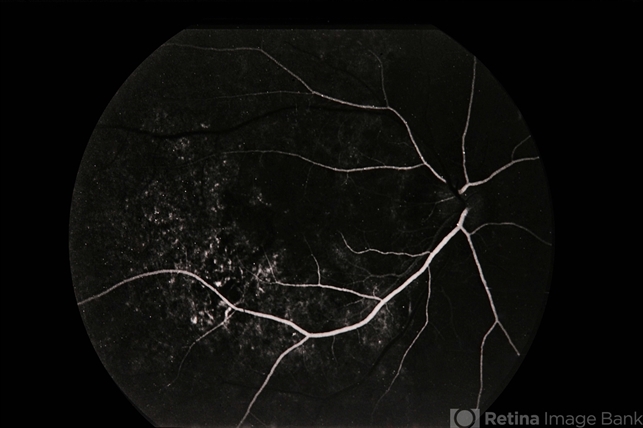

Pseudo-POHS / Lyme

presumed ocular histoplasmosis syndrome (POHS), Lyme disease

Pseudo-POHS / lyme.